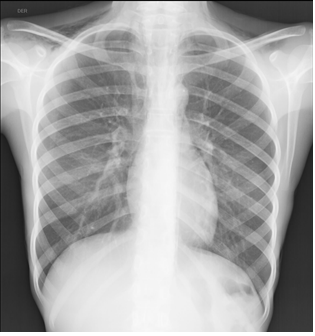

Presentamos el caso de una adolescente de sexo femenino quien cumple criterios clínicos de anorexia nerviosa y presenta dolor torácico, documentándose pneumomediastino espontáneo (PE). El PE se define como presencia de gas libre en el mediastino en ausencia de causa precipitante.

Clínicamente, el síntoma principal es el dolor torácico, seguido de disnea y a la exploración física es importante reconocer signos específicos, de los cuales el más frecuente es el enfisema subcutáneo, así como el signo de Hamman considerado patognomónico.